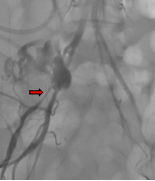

患者,女,50岁,主因腹膜后恶性肿瘤术后出现引流管出血逐渐增加,转入我科行介入治疗,造影提示:右侧髂外动脉中段造影剂外渗、局部大片造影剂滞留,考虑髂外动脉破裂出血,行4*40mm球囊以6atm压迫止血后造影出血明显减少,遂行髂外动脉覆膜支架植入术彻底解决患者出血问题,为患者后续治疗。

术前造影 球囊压迫止血后造影 支架植入术后